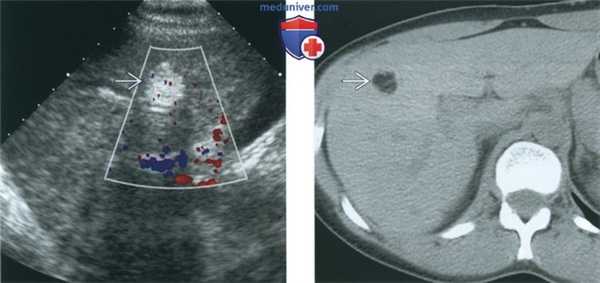

(Слева) На ультрасонографии определяются два узла Рокитанского в жире дермоида, имеющего противоречиво кистозный вид.

(Справа) На цветовой допплерографии определяется плавающий полутвердый - полужид -кий жир в дермоиде, жидкостно-жировой уровень.

(Слева) При ТАУЗИ в сагиттальной плоскости у пациентки 27 лет, выполненном через 8 мес. после операции по поводу незрелой тератомы и последующей химиотерапии, в правой доле печени выявляется объемное образование высокой эхогенности.

(Справа) При нативной КТ в аксиальной плоскости у той же пациентки в печени визуализируется объемное образование жировой плотности, которое имелось и на ранее полученных КТ. Отклонения в уровне а-фетопротеина и β-ХГЧ отсутствовали (уровень α-фетопротеина вначале был повышен). При биопсии объемного образования печени выявлены только элементы зрелой тератомы. Данный случай является примером синдрома растущей зрелой тератомы.